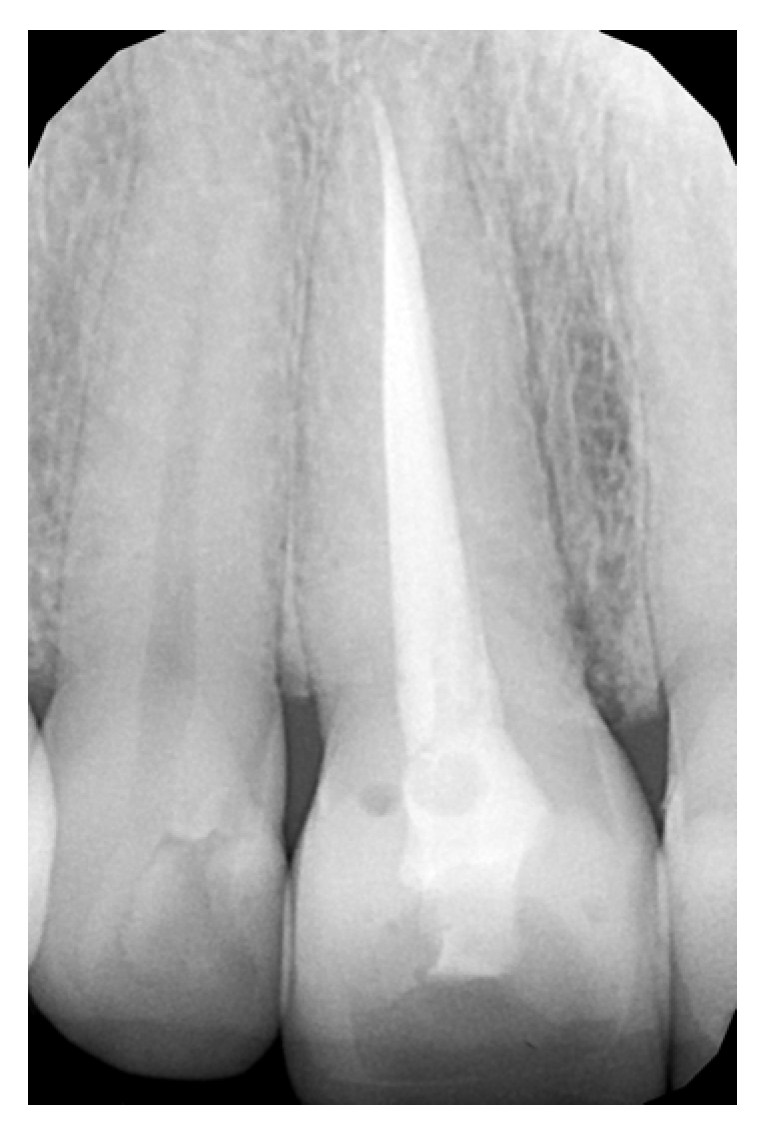

2.2. Pre-Treatment Procedures

2.3. Tooth Preparation Procedure